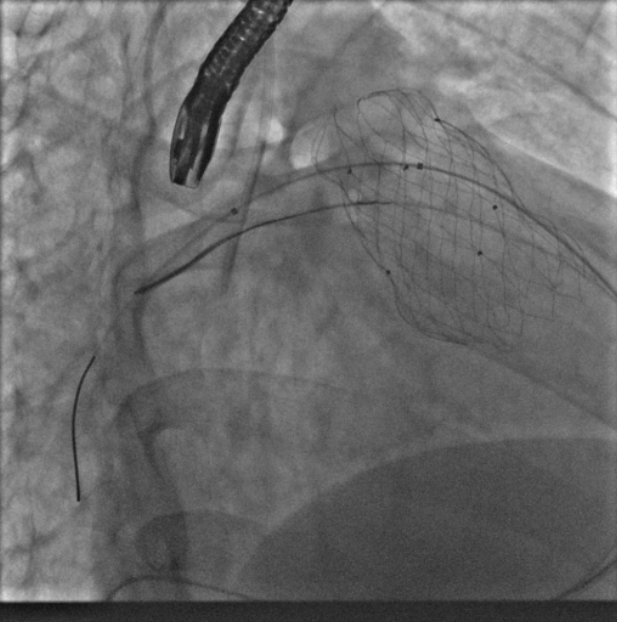

术中测量患者基础主动脉、肺动脉、右心室压力分别为111/58mmHg、31/4/13mmHg、34/1/6mmHg,通过肺动脉造影,术中测量球囊内径为32mm(见图二),选择36-25mm VENUS-P肺动脉瓣膜,在肺动脉造影指引下逐步打开瓣膜。考虑到患者肺动脉分叉较短,存在瓣膜释放后移位风险,故选择高位释放法(图三)。但释放瓣膜后造影提示右肺动脉开口局部被阻挡(图四),复测患者主肺动脉、左肺动脉、右肺动脉压力分别为57/13/25mmHg、55/12/24mmHg、27/7/14mmHg。

图三:考虑到患者肺动脉分叉较短,选择高位释放法